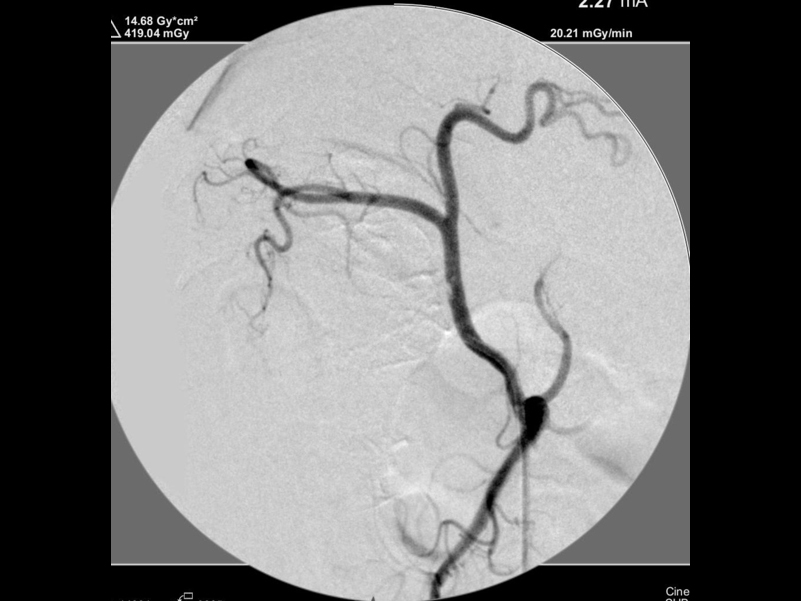

腫瘍塞栓後の造影検査

術後の止血している様子